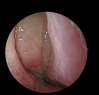

Poliposi nasale

La poliposi nasale è una forma di rinosinusite cronica caratterizzata dalla presenza di estroflessioni delle mucose, marcatamente infiammate ed edematose, che prendono il nome di “polipi”. Ha un’incidenza di circa l’1-2% nella popolazione generale ed ha un importante impatto sulla qualità di vita. La terapia si basa sull’utilizzo di farmaci corticosteroidei nasali e nei casi più severi è necessario un intervento di chirurgia endoscopica nasale. Negli ultimi anni sono stati approvati nuovi farmaci monoclonali per il trattamento di questa patologia, indicati soprattutto nelle forme severe e ricorrenti.